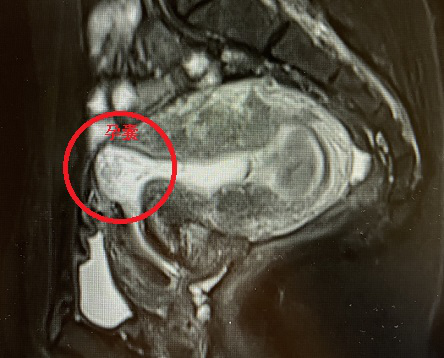

什么是瘢痕妊娠? 瘢痕妊娠的病因及高危因素 瘢痕妊娠的临床表现及诊断 疤痕妊娠的分型 瘢痕妊娠的危害 瘢痕妊娠的预防 本文内容转载自“上海市同仁医院妇产科”微信公众号 延伸阅读